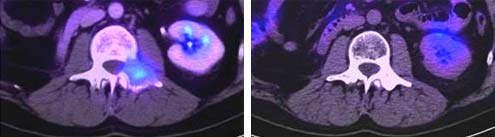

Auf dem linken Bild zeigt sich im PET-CT eine Wirbelsäulenmetastase eines Nierenzellkarzinoms vor der einmaligen Cyberknife Behandlung. Auf dem rechten Bild zeigt sich der Status 6 Monate nach der Cyberknife Behandlung. Der Tumor ist nicht mehr nachweisbar und der behandelte Bereich ist wieder verknöchert.